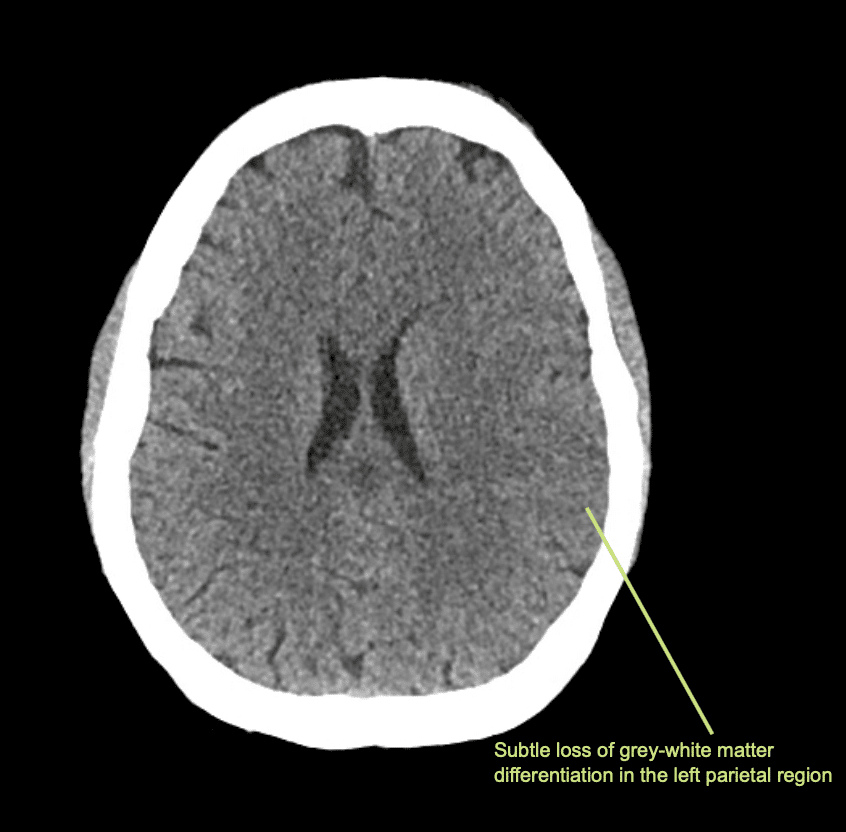

Il giorno successivo viene eseguita una TAC di controllo.

Interpretazione della TAC a 24 ore